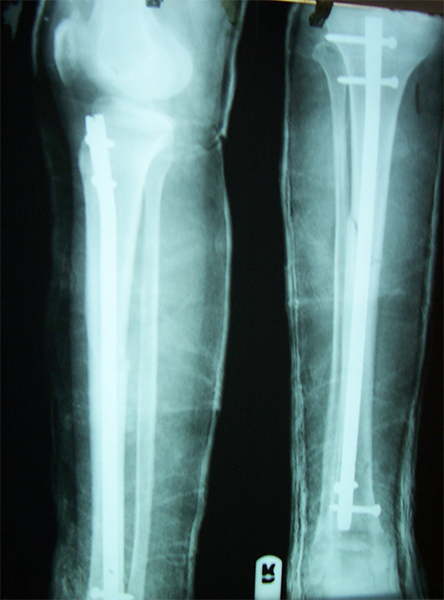

Case:8 Polytrauma

Patient having closed segmented fracture midshaft & lower 1/3 Tibia with closed fracture superior & inferior pubic rami right side with pelvis fracture following vehicular accident wastreated with intramedullary nail for fracture tibia and external fixator for fracture pelvis.

Pre-Op

Immdiate Post-op

Post-op Lateral

Lat-Post Fall

Ex fix with frame

Post-op 1 and half months follow-up

Post Uninon-3Months